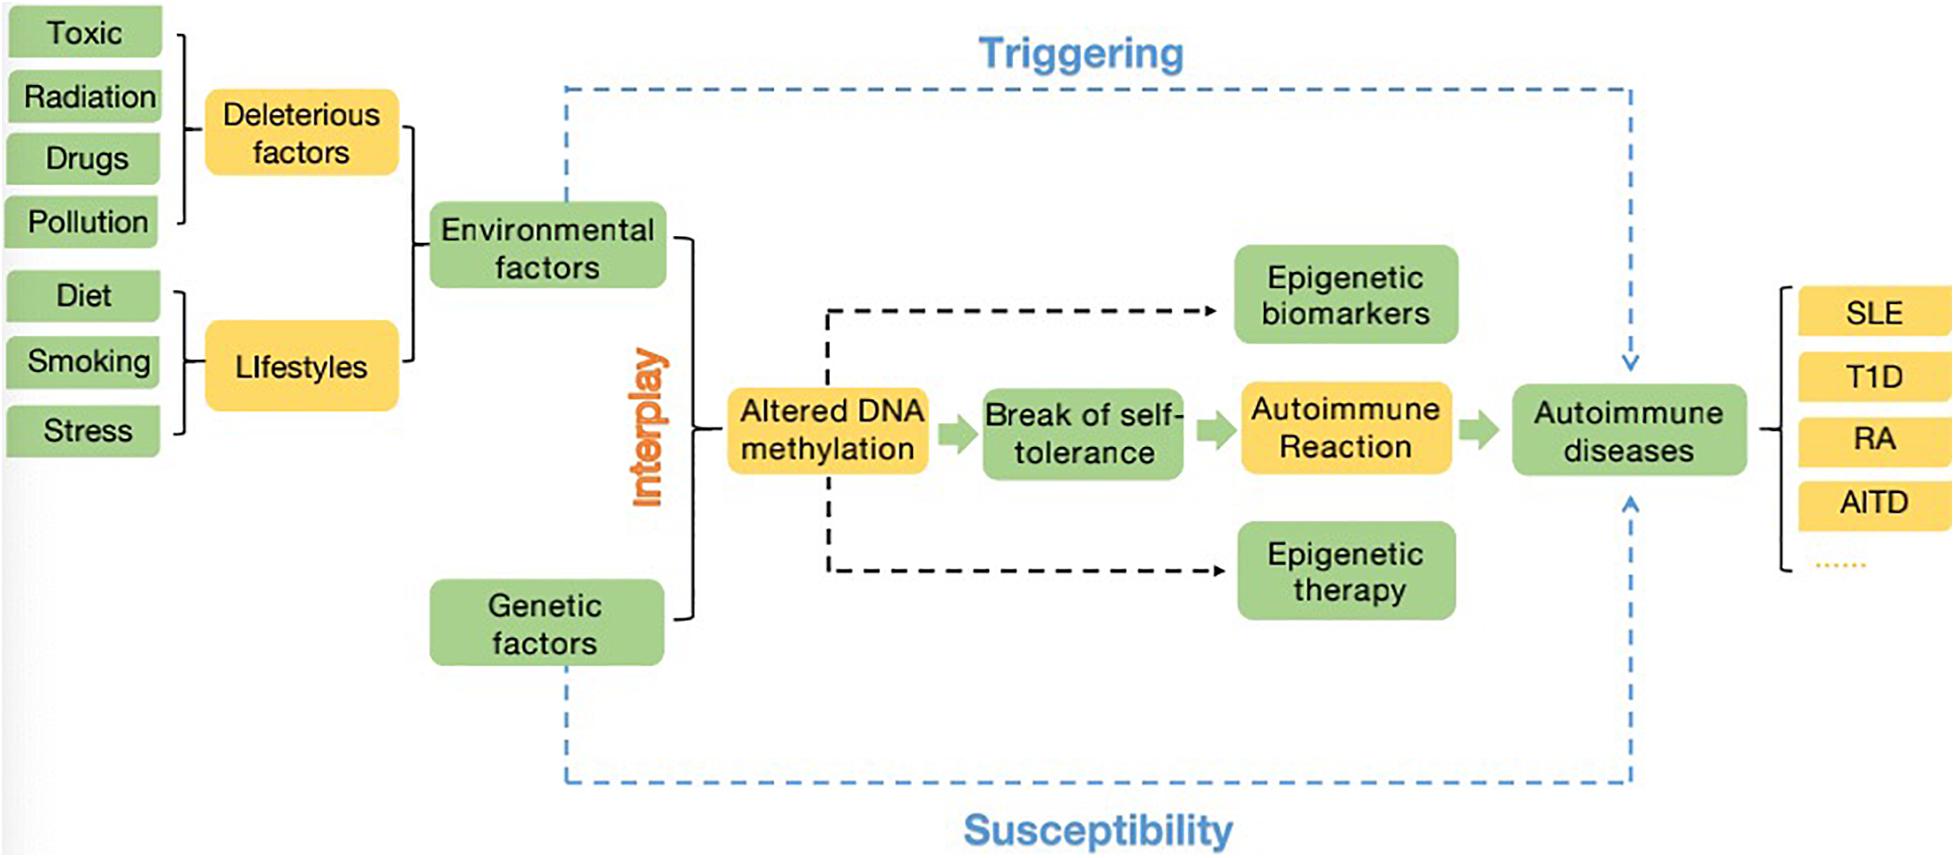

Frontiers | Insights Into the Role of DNA Methylation in。Therapeutic potential of plant-derived natural compounds in。Association of oral health with all-cause and cause-specific。商品名【新品】グラッチェア バランスチェア 姿勢矯正オフィスチェア 椅子 レッド 腰痛製品詳細グラッチェア バランスチェア主な特徴デザイン: スタイリッシュなレッドカラーのバランスチェアで、オフィスや自宅での使用に最適です。機能: 姿勢矯正を目的として設計されており、骨盤をサポートし、腰痛を軽減します。使いやすさ: 軽量で持ち運びやすく、様々な場所で快適に使用できます。付属品写真のものが全てになります!保管時のこすれ等がある場合がございますが、本体や性能に問題ございません。ご理解できる方宜しくお願い致します。細かな点が気になる方、保管品に不慣れな方は購入はご遠慮ください。最後までご閲覧頂き、誠にありがとうございます。すり替え等防止のため返品不可とさせていただきます。プチプチにて発送させていただきます。。Elucidation of the Mechanism of Occasional Anterior。☆ZAMST ZW-7 腰痛ベルト Mサイズ☆。【美品】柔ら美人 開脚ベター イージースリム ディノス dinos。Lサイズ ガードナーゴルフベルト GUARDNER GOLF BELT。SIXPADパワースーツライトコアベルト。【美品】MTG Style PREMIUM 骨盤矯正クッション。MTG スタイルアスリート Style Athlete ソリッドブラック最安値!。【新品】スタイル プレミアム デラックス 骨盤 姿勢 猫背 補正 座椅子 黒。フィットキープ2 骨盤ベルト Lサイズ【本日限定価格】